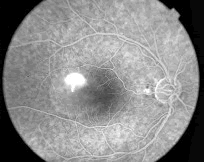

B超检查:左眼下方高回声占位, 如图40-3所示。

荧光血管造影:早期可见肿物处血管充盈, 随时间,荧光逐渐增强, 局部伴出血荧光遮蔽,晚期可见血管渗漏, 伴周围网膜下渗出性改变,如图40-4所示。